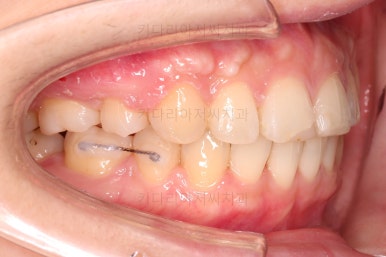

우선 장치를 부착해요.

환자분이 선택하신 장치는 엠파워 클리어라고 하는 자가결찰 세라믹 장치에요.

흔히들 클리피씨라고 많이 알고 계신 장치도 자가결찰 세라믹 장치의 한 종류에요.

제조사가 일본(클리피)이냐 미국(엠파워)이냐의 차이일 뿐이죠.

교정장치를 부착한 직후의 모습인데요.

눈에 보이는 장치의 모습과 입매의 변화를 참고해 주세요.

치아를 뽑은 위치, 당겨야 할 정도가 달라 미니스크류를 몇 개 사용했어요.

미니스크류는 앞뒤조절, 높낮이 조절, 각도 조절, 안밖의 위치조절 등 난이도 높은 치료를 가능하게 해준답니다.